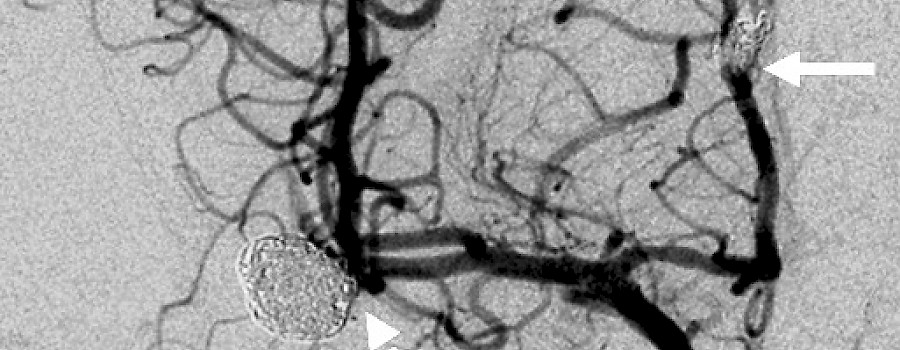

Durch Aneurysmascreening familiär vorbelastete Patienten schützen.

Was ist heute auf unserem ominösen Röntgenbild abgebildet?